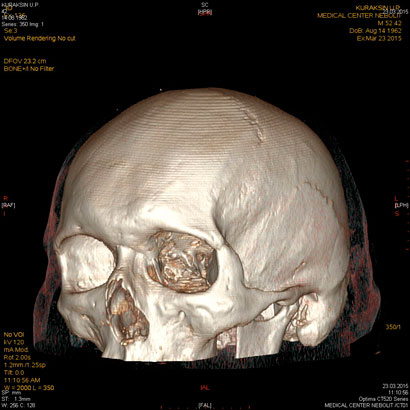

МСКТ головного мозга.

С появлением КТ значение обычной рентгенографии в выявлении переломов черепа значительно уменьшилось, назрел вопрос о пересмотре диагностической тактики при ЧМТ. В настоящее время следует считать правилом, что при наличии соответствующей аппаратуры в первую очередь необходимо проведение компьютерной томографии.

МСКТ является прекрасным методом выявления травматических повреждений, гематом, переломов, ретробульбарного скопления воздуха. КТ и МРТ обладают одинаковой чувствительностью в выявлении орбитальных опухолей: глиома, менингиома, лимфангиома, гемангиома, гемангиопероцитома и др, а также внеконусных образований: опухоли слезной железы, дермоид, лимфома, псевдоопухоли, метастазы, тиреоидная миопатия.

КТ и МРТ обеспечивают хорошую визуализацию турецкого седла. Однако МРТ обладает рядом преимуществ-более хорошее мягкотканое разрешение, недостаток-плохо видит кальцинаты. В свою очередь МСКТ является методом выбора при всех неотложных состояниях с травмами головы.

МСКТ остается методом выбора и особенна эффективна при обызвествлениях, инородных тел, костных структур. Некоторые опухоли нр гемангиома лучше видны при МРТ. При бактериальных поражениях мозга-абсцессах, менингитах,эмпиемах могут возникать трудности диагностики с опухолевым поражением, что требует введения контраста.

Клинические показания:

- травма головного мозга, лицевого черепа с подозрением на внутричерепное или субарахноидальное, субдуральное кровоизлияние, посттравматические последствия

- дифференциальная диагностика геморрагического и ишемического инсульта

- диагностика венозного тромбоза, внутримозговых гематом, САК

- подозрение на опухоль и вторичное поражение

- подозрение на воспалительный процесс (абсцесс)

- головная боль быстро прогрессирующая или длительная до 2 мес, не объясняемая другими причинами

- изменения в костях свода и основания черепа

- диагностика селлярных опухолей при невозможности проведения МРТ

Подготовка: не требуется

Предварительное рекомендуемое обследование: заключение невролога МСКТ головного мозга с вв усилением необходима при подозрении на опухолевый процесс, инфекционное поражение.